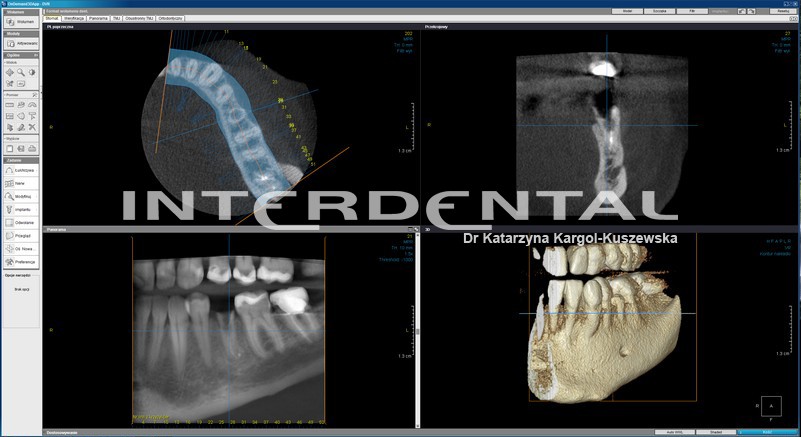

CBCT - tomografia komputerowa w stomatologii

CBCT (Cone-beam computed tomography in dentistry) – jest szybką a zarazem bezpieczną metodą obrazowania w radiologii stomatologicznej. Tomograf komputerowy CBCT pozwala na uzyskanie trójwymiarowego obrazu twarzoczaszki przy znacznie niższej dawce promieniowania w stosunku do konwencjonalnej tomografii komputerowej CT.  CBCT jest najdokładniejszą metodą obrazowania w stomatologii, chirurgii szczękowo-twarzowej oraz laryngologii.

W powstałym obrazie widoczne są kanały nerwowe, naczynia krwionośne, zęby, zatoki oboczne nosa. CBCT pozwala na obrazowanie wszystkich struktur anatomicznych z dokładnością niemożliwą do uzyskania w innym rodzaju badania radiologicznego. Uzyskany obraz można wielokrotnie przetwarzać, obrabiać, mierzyć i tworzyć wizualizację.

W naszej klinice posiadamy cyfrowy aparat tomograficzny Scanora 3Dx o zwiększonej ilości pól obrazowania od małego S (zastosowanie endodoncja, zęby zatrzymane) do największego XL+ (znajdującego zastosowanie w chirurgii szczękowo-twarzowej i laryngologii dla obrazowania zatok przynosowych, nosa, ucha i gardła).

Implantologia

• ocena jakości i ilości kości

• ocena położenia przyszłych implantów w stosunku do struktur anatomicznych nerwów, zatok szczękowych, korzeni zębów

• kontrola pozabiegowa oraz ocena powodzenia przeszczepu kości oraz wszczepionych implantów

• wizualizacja planowanego położenia implantów